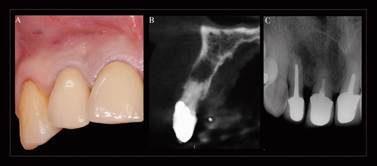

Paciente sexo femenino, 61 años de edad, ASA I, quien acude a la Facultad de Odontología de la Universidad de Chile consultando por trauma dentoalveolar en diente 1.2 rehabilitado con prótesis fija unitaria metal cerámica. El examen imagenológico muestra área radiolúcida periapical (Figura 1).

Se realiza sindesmotomía con periótomo y posteriormente extracción vertical atraumática del diente 1.2 con extractor dental Neodent® (Neodent, Curitiba, Brasil), luego se acondiciona mecánicamente el alveolo dentario con cuchareta y abundante irrigación con solución salina fisiológica para eliminar tejido inflamatorio e infeccioso que pudiera haber quedado posterior a la exodoncia (Figura 2).